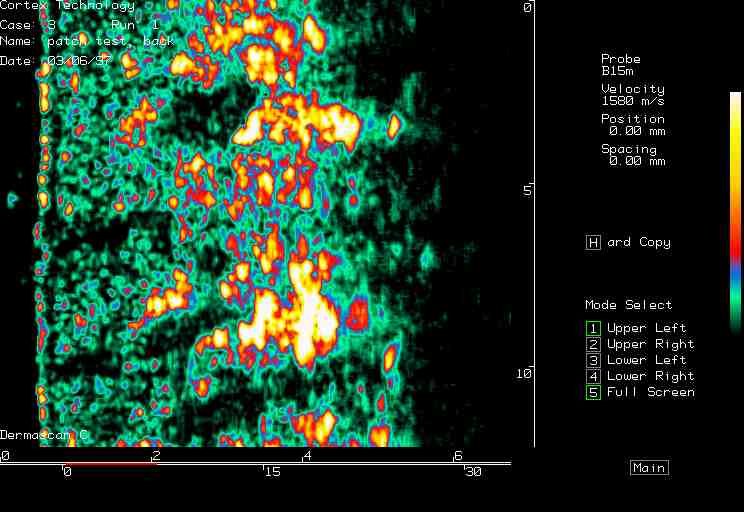

20 MHz 2D images

| Reactions |  Irritant reaction |

Patch test, back |